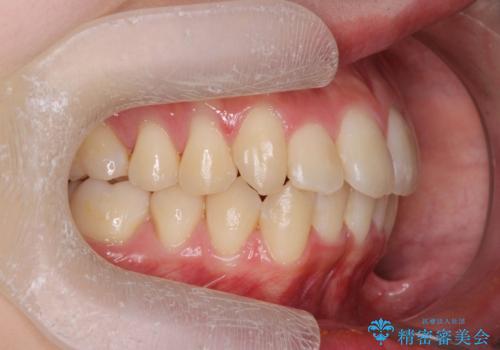

前歯のがたつきをマウスピース矯正できれいに!

- 目立つ前歯のがたつきを改善したい、と矯正治療を希望され来院されました。

今回の治療ではシミュレーションでしっかりと検討した結果、下顎は前歯を1本抜去し仕上げる治療計画としました。